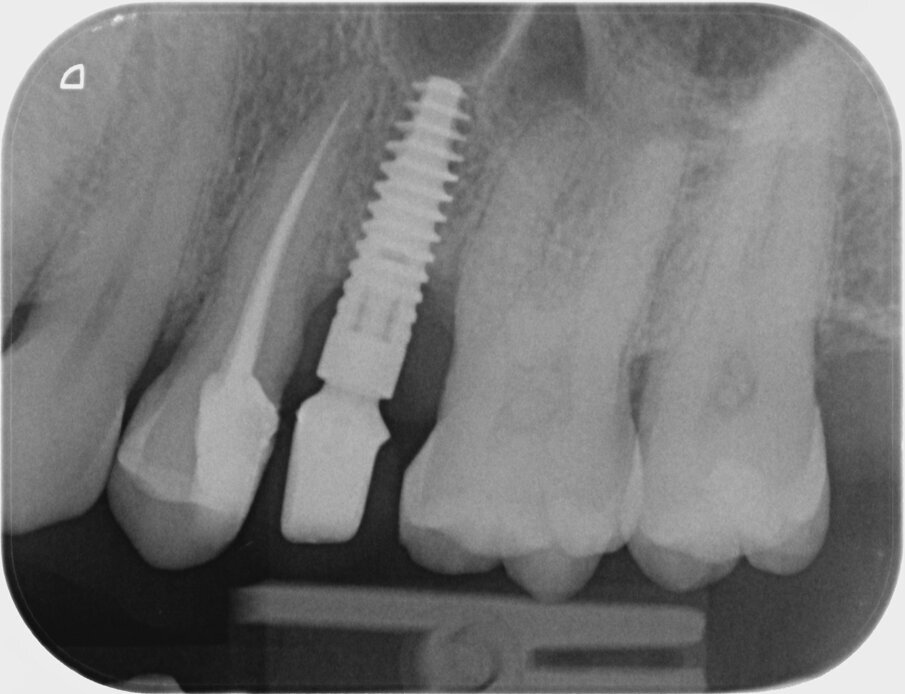

Quinta e sesta seduta A 90 gg si effettua seduta di richiamo con deplaquing, privilegiando l’impiego di polvere di glicina con sistema air polishing (CombiTouch Mectron Spa) con multidirezionalità del getto prima in senso apico-coronale, poi in direzione corono marginale e infine perpendicolare alla superficie implantare esposta, con l’obiettivo di decontaminarla al meglio, senza ledere i tessuti circostanti. A 6 mesi dal baseline (t4) si esegue la rivalutazione. Vengono eseguite fotografia e rx endorale del sito di controllo (Figg. 5, 6). All’esame visivo e palpativo i tessuti molli perimplantari si presentano in buono stato, in termini di colore e consistenza. All’esame radiografico si apprezza una remineralizzazione dell’osso. Viene eseguita la terapia professionale mediante la medesima tecnica di air polishing con polveri a bassa granulometria, al fine di disgregare l’eventuale biofilm patogeno, potenziale causa di recidiva. In entrambe le sedute viene eseguito un rinforzo motivazionale.

Fig. 5

Fig. 6

È possibile apprezzare radiograficamente un’aumentata mineralizzazione ossea, con un ulteriore miglioramento rispetto alla prima rivalutazione post-terapia. Questo dato indica la risoluzione dello stato infiammatorio cronico e conferma il buon potenziale rigenerativo della terapia adottata. Contestualmente, all’esame visivo dei tessuti, si osserva un riposizionamento in direzione coronale del tessuto molle, con un aumento dei volumi gengivali rispetto al tempo t4, anch’esso indicativo del potenziale rigenerativo stimolato dalla strategia terapeutica a livello del tessuto connettivo gengivale.